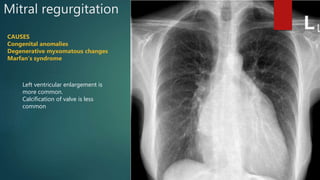

Mitral regurgitation

CAUSES

Congenital anomalies

Degenerative myxomatous changes

Marfan’s syndrome

Left ventricular enlargement is

more common.

Calcification of valve is less

common